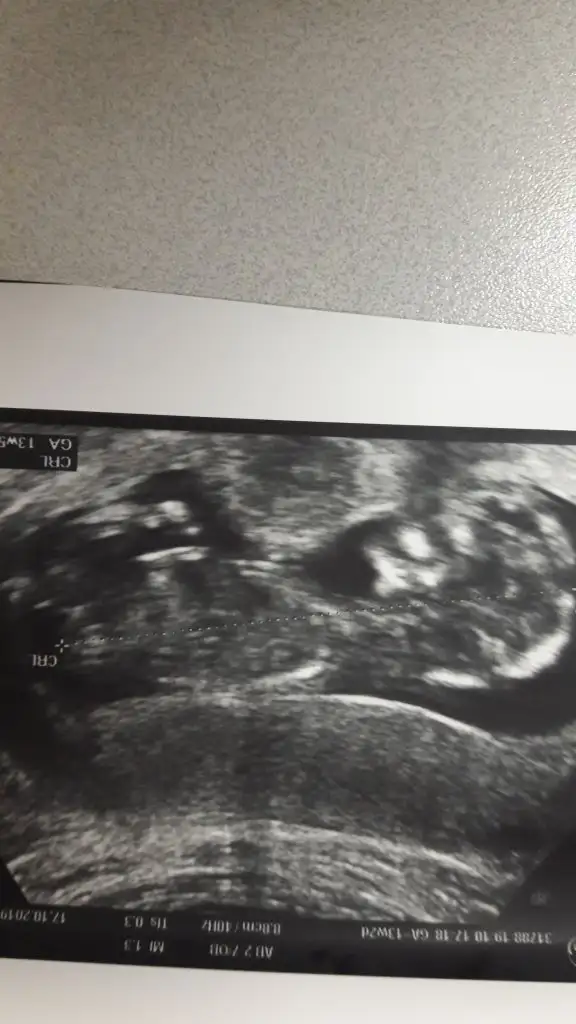

Hayırlısı sağlıkla gelsin inşallah bence ikizEvet canim aynen.Yok kesin bi sey soylemedi.Bi hafta sonra tekrar cagirdi.Iki yumurtam vardi .Bakalim nolucak.Beklemek cok zor

Cok tesekkur ederim .Insallah kesinlessin paylasicamHayırlısı sağlıkla gelsin inşallah bence ikiz

İki kese arasında fark var biri gider yada kalır canım hayırlısı olsun senin için 8 hafta netleşir 2 kalp sesi duymak nasip olsun